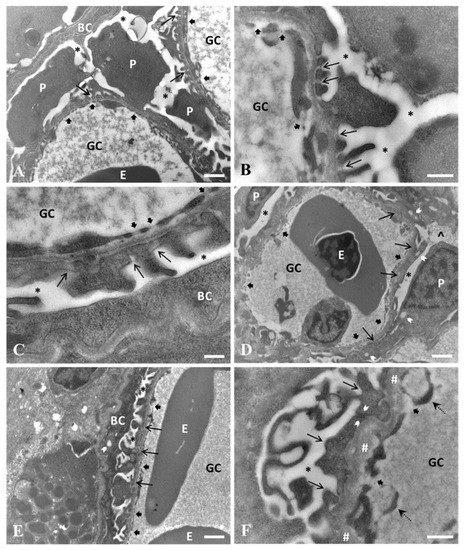

Ultrastructural Alterations of the Glomerular Filtration Barrier in Fish Experimentally Exposed to Perfluorooctanoic Acid